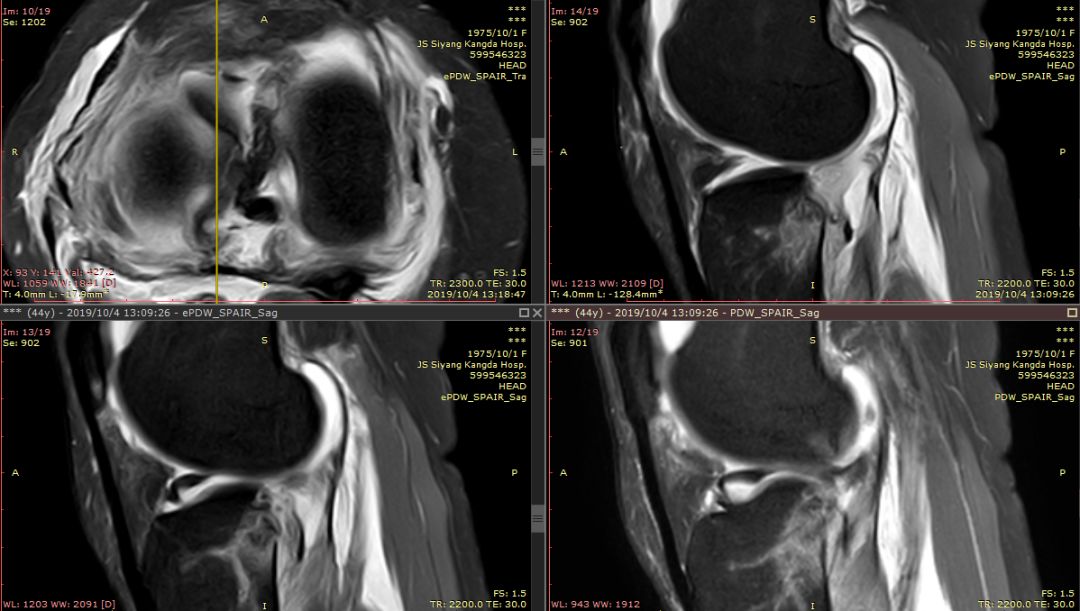

Segond骨折,因下肢过度内翻、内翻暴力所致胫骨平台外侧缘的撕脱性骨折。撕脱的骨折块较小,小骨片多位于腓骨头上方,且较少波及关节面而易被忽视。往往合并前交叉韧带损伤、半月板损伤及外侧副韧带损伤。

有文献报道,Segond 骨折合并有前交叉韧带(ACL)损伤的发生概率约为75%~100%,若没有得到及时处理,关节将会出现反复扭伤的现象,容易引发膝关节继发性损害,最终将导致关节过早的出现退变和骨关节病的发生。当怀疑Segond骨折,应该做MRI检查,评价膝关节组织损伤情况。